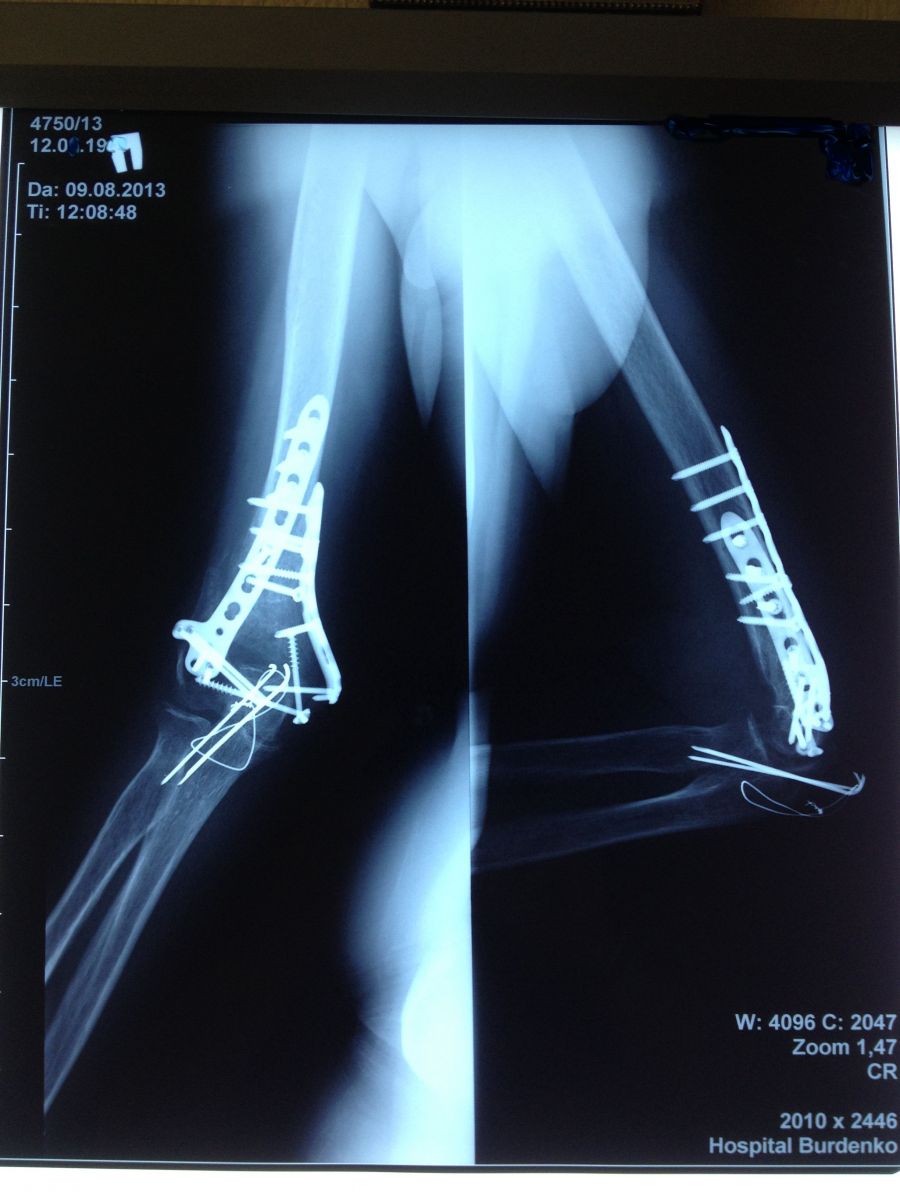

Рис. 3. Пациентка, 52 года. Закрытый внутрисуставной оскольчатый перелом нижней трети правой плечевой кости со смещением костных отломков. Закрытый внутрисуставной перелом локтевого отростка правой локтевой кости со смещением костных отломков.

Рис. 4. Пациентка, 52 года. Нижняя треть правой плечевой кости, фиксированная пластинами и винтами. Локтевой отросток правой локтевой кости, фиксированный спицами Киршнера и проволокой по Веберу.